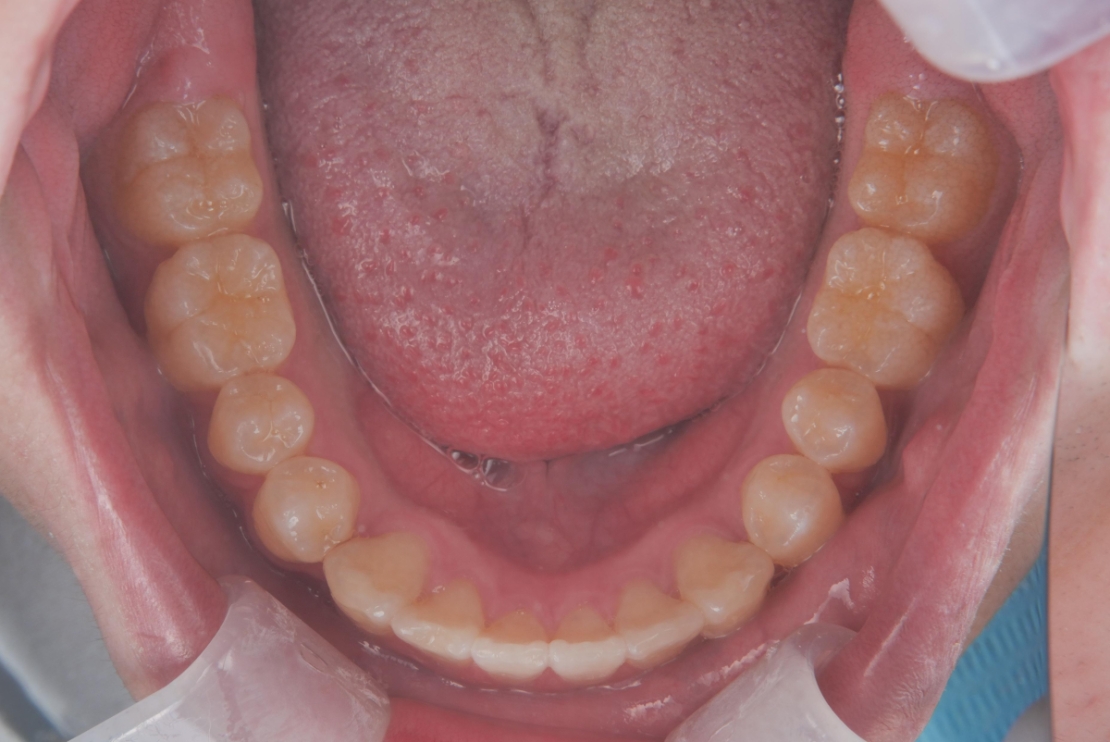

BEFORE

AFTER